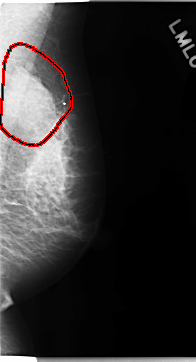

C_0113_1.LEFT_MLO

LEFT_MLO LINES 4696 PIXELS_PER_LINE 2536 BITS_PER_PIXEL 12 RESOLUTION 50 OVERLAY

FILE: C_0113_1.LEFT_MLO.OVERLAY

TOTAL_ABNORMALITIES 1

ABNORMALITY 1

LESION_TYPE MASS SHAPE LOBULATED MARGINS MICROLOBULATED

ASSESSMENT 5

SUBTLETY 5

PATHOLOGY MALIGNANT

TOTAL_OUTLINES 1

BOUNDARY